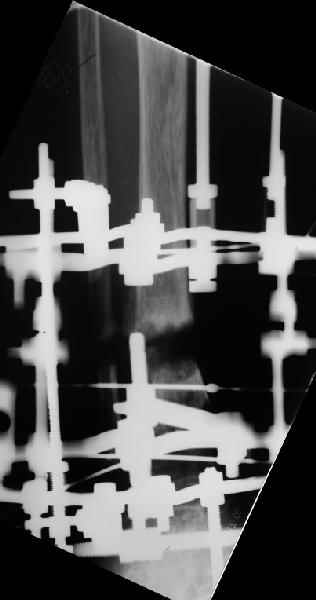

Аппарат - чтобы плавно исправить ось. В приложении - снимки на момент окончания коррекции в аппарате, фото с операции, и послеоперационная рентгенограмма.

Диаметр гвоздика 10,5 мм. Пришлось укорачивать до 23 см - уж очень миниатюрная дама, отверстия насверлил под 45 градусов, под 5 мм винты. По оси удалось сблизить до этого положения. Заперли гвоздь пока статически с планом через 2 месяца верхний винт убрать. Но это ей придется уже в Ташкенте сделать. Что скажете? Спасибо.

In attachment - x-rays at the end of alignment, the surgery, and result. The nail was cut to 23 cm. Four 45 degree holes were pre-drilled at the distal nail tip. The nail was locked statically

after some impaction. Dynamization is considered in 8 weeks. Any comments/critics?

Отправитель: Nuno Craveiro Lopes 27 Апрель 2005, 02:10

Alex,

> In attachment - x-rays at the end of alignment, the surgery, and

> result. The nail was cut to 23 cm. Four 45 degree holes were

> pre-drilled at the distal nail tip. The nail was locked statically

> after some impaction.

Amazing! How can you find the pathway of the nail through all those wires and the distal screws through so much hardware?